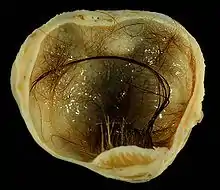

A small (4 cm) dermoid cyst of an ovary, discovered during a C-section

A dermoid cyst is a teratoma of a cystic nature that contains an array of developmentally mature, solid tissues. It frequently consists of skin, hair follicles, and sweat glands, while other commonly found components include clumps of long hair, pockets of sebum, blood, fat, bone, nail, teeth, eyes, cartilage, and thyroid tissue.